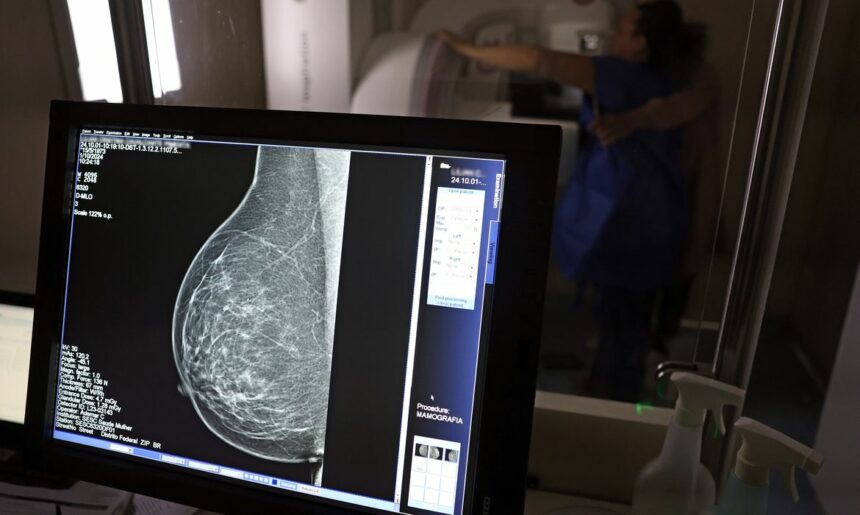

Um estudo de cientistas norte-americanos que identificou moléculas de RNA com potencial terapêutico no tratamento do câncer de mama é objeto de análise pela Sociedade Brasileira de Mastologia (SBM Rio).

Mas independentemente da terapia, o que faz a diferença no tratamento é o reconhecimento dos sintomas e as práticas de monitoramento e prevenção, como destaca o presidente da Sociedade Brasileira de Mastologia, Eduardo Bruno Giordano.

“O sucesso do tratamento do câncer de mama depende do diagnóstico precoce e tratamento adequado. Eu acrescentaria, ainda, o tratamento em tempo adequado, que não se postergue o início do tratamento. No início do menor sintoma, que se procure ajuda. É importante que você, mulher, procure seu médico para solicitar o exame. E que os homens incentivem suas esposas e parentes de forma regular”.